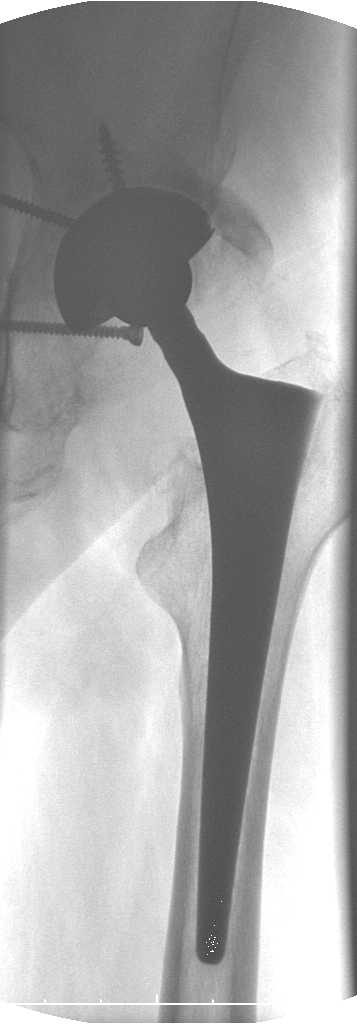

Уважаемые коллеги.В 3 Центральный Военный Клинический Госпиталь имени А. А. Вишневского, что в Красногорске, Московской области, в отделение эндопротезирования крупных суставов поступил пациент 1960 года рождения Жалобы при поступлении: на боли в области левого тазобедренного сустава (больной указывает на точку расположенная в середине условной линии между седалищным бугром и большим вертелом), усиливающиеся в начале ходьбы, при опоре на левую ногу с иррадиацией болей по наружной и наружно-задней поверхности левого бедра, левый коленный сустав; снижение объема движения в левом тазобедренном суставе, снижение опорной способности левой нижней конечности, хромоту на левую ногу, необходимость использования дополнительной опоры (костыли) при ходьбе, снижение объема двигательной активности из за болей в суставе.В анамнезе: Со слов больного, согласно медицинских документов, в 1989 году получил травму левой нижней конечности: закрытый перелом левой вертлужной впадины с центральным вывихом головки левой бедренной кости. Лечился консервативное. В процессе лечения сформировался посттравматический артроз, укорочение левой нижней конечности до 5 см. 25.04.2005 года в Подольском Окружном Госпитале Министерства Обороны выполнено: одномоменто, остеосинтез заднего края вертлужной впадины фрагментом резецированной головки бедренной кости и тотальное эндопротезирование левого тазобедренного сустава бесцементным эндопротезом "VERSIS ET" с бесцементной чашкой TRILOGY. Послеоперационный период осложнился ранним нагноением области эндопротеза, в результате санаций очага инфекции и антибиотикотерапии, активного промывного дренирования антисептиками, послеоперационная рана зажила. После операции, со слов больного, через два месяца в полном объеме стал нагружать левую нижнюю конечность. В течение полгода, после операции чувствовал себя вполне удовлетворительно. С марта 2006года стал отмечать появление болей в области тазобедренного сустава, то в области паха, то в области левой ягодицы. С августа месяца отмечает те жалобы, с которыми он сейчас к нам обратился. Температура тела, после заживления раны, нормальная. В анализах крови, лейкоциты около 7 тыс, формула нормальная, СОЭ 12 мм ч. Локально: при осмотре обеих нижних конечностей, анатомическая ось конечности не нарушена; отмечено относительное укорочение левой н\конечности на 1.5 см., гипотрофия мышц левого бедра 3 см, голени 2 см, симптом. Объем движений в тазобедренных суставах: правый~ сгибание- 60 гр, разгибание-180 гр ,отведение- 35 гр, левый~ сгибание- 110 гр , разгибание-170 гр , отведение-15 гр. Контуры других суставов н/конечностей обычные, объем движений в них не страдает. Пульсация на артериях конечностей удовлетворительная. Неврологические нарушения конечностей отсутствуют, рефлексы на обеих н/конечностях одинаковые, чувствительных нарушений нет. Осевая нагрузка на левую нижнюю конечность вызывает боль в точке расположенная в середине условной линии между седалищным бугром и большим вертелом. Отмечается пигментация и пастозность нижней трети обеих голеней и стоп, характерная для посттромботической болезни. На Цветном дуплексном сканировании сосудов нижних конечностей: Нестенозирующий атеросклероз обеих бедренных и подколенных артерий . Гемодинамически значимых препятствий кровотоку в магистральных артериях ног не выявлено. Глубокие и поверхностные вены нижних конечностей проходимы. Умеренная недостаточность клапанов подколенных вен. Данных за тромбоз глубоких вен на момент осмотра не получено.А вот что пишет наш рентгенолог: На серии рентгенограмм области левого тазобедренного сустава определяется тотальный бесцементный эндопротез. Вокруг тени чашки эндопротеза определяется ободок остеорезорбции. Кроме того, визуализируется деформированный костный винт фиксирующий консолидированный отломок вертлужной впадины, вплотную прилегающий к тени чашки эндопротеза. Заключение: Рентгеновские признаки нестабильности чашки тотального эндопротеза. Лучевая нагрузка: 6 мЗв. У нас в отделении разошлись мнения: начальник мой утверждает, после сравнения снимков, принесенных больным от августа и октября 2006года и наших рентгенснимков, что у больного нет нестабильности вертлужного компонента, и что надо назначит курс консервативной терапии: препараты кальция, миакальцик, увеличить осевую нагрузку на левую нижнюю конечность, ЛФК направления на укрепление мышц бедра, ягодиц, физиолечение. А я утверждаю, что у больного клиника нестабильности вертлужного компонента, и необходима ревизия вертлужного компонента, не исключено даже наличие инфекции под чашкой эндопротеза (не смотря на отсутствие клинических признаков инфекции). В результате проводимой консервативной терапии, боли у больного усилились. Помогите рассудить нас, мы готовы выслушать ваши мнения по этому поводу. С уважением Батал Шушания.3 ЦВКГ имени А. А. Вишневского

уважаемый коллега, Антон Вакуленко. Спасибо за четкий, расписанный по пунктам план действий. При поступлении пациента в отделение, я думал точно как вы. Но на следующий день, выполнил многопроеционное рентгенисследование, показал невропатологу, и доложил начальнику отделения о больном.После разбора пришли к следующему, да у больного действительно нестабильность вертлужного компонента, есть зона лизиса в месте костного аутотрансплантата, а в месте фиксаци чашки деротационным винтом четко выраженный контакт чашки с костной тканю. Мы пришли к выводу,что лизис костного аутотрансплантата из за осевой перегрузки на фоне незавершенного ремоделирования (вес больного 130 кг). Потому мы и приняли план вышеуказанного лечения. Провели беседу с больным, больной согласился с нами. Через 3-6 месяцев мы оценим эффективность лечения и доложу. Возможно и придется тогда идти на ревизию с заменой только вертлужного компонента а может и придется удалить весь эндопротез с установкой спейсера.. посмотрим.....